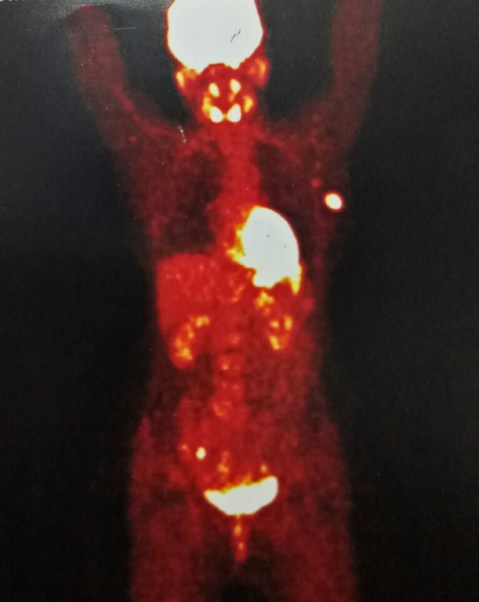

MRM for breast cancer, with PET scan showing axillary mets. 45 years old, c/o dr Jasleen.

5.1.19